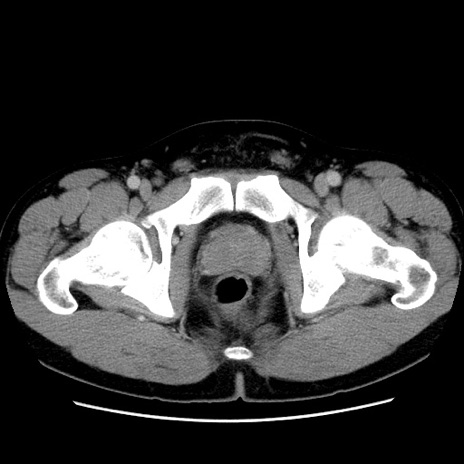

症例4(横断像)

【症例】30歳代男性

【主訴】腹痛、嘔吐

【現病歴】昨晩から突然の腹痛あり、その後嘔吐、軟便も出現。腹痛が改善しないため救急搬送となる。2日前にしめ鯖の食事歴あり。

【身体所見】意識清明、苦悶様、BP 135/90mmHg、BT 35.7℃、腹部:平坦、やや硬、心窩部〜臍部に自発痛、圧痛あり、筋性防御+、反跳痛-

【データ】WBC 8100、CRP 0.57